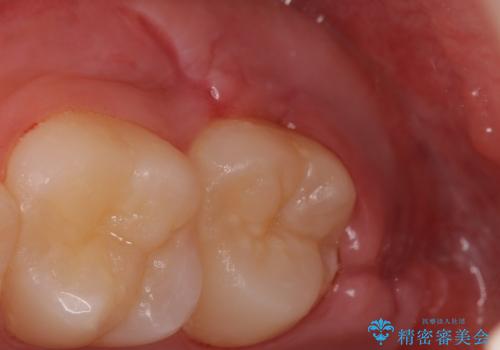

親知らずは入院せずとも通院で片側上下同時に抜くことが可能です。

手前の歯の虫歯リスクを下げるためにも、骨から出てきた親知らずは抜くことをお勧めします。

また術後丁寧に縫合をすることで治癒後の歯茎の状態もきれいにすることができます。